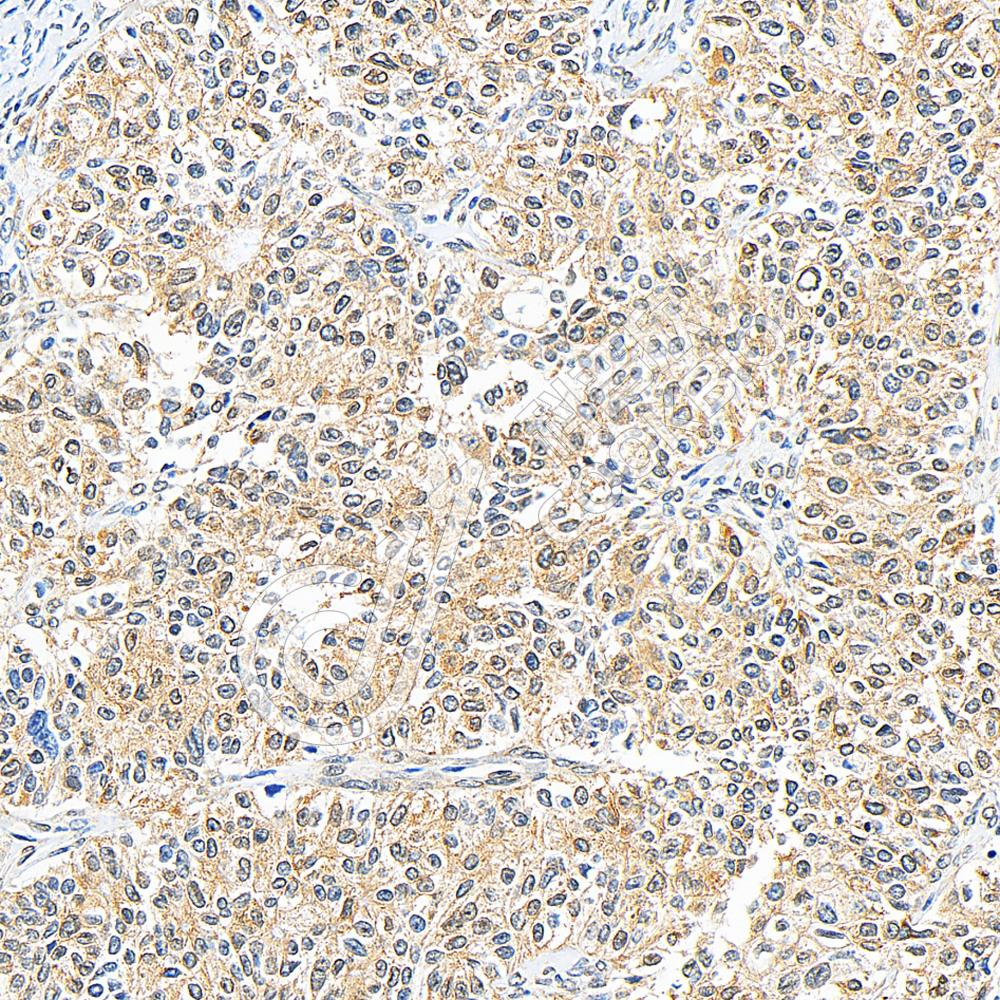

IHC检测GSK3 beta蛋白(货号 K1335082).

样品: 人卵巢癌, 4%多聚甲醛 (货号KSG1101) 固定12-24小时.

抗原修复: 柠檬酸抗原修复液(干粉, pH 6.0) (KSG1201), 98℃, 20分钟.

—抗: 1: 800稀释, 4℃ 孵育过夜.

二抗: S-vision免疫组化多聚二抗(山羊抗兔),即用型 (货号KB3906), 室温孵育20分钟.